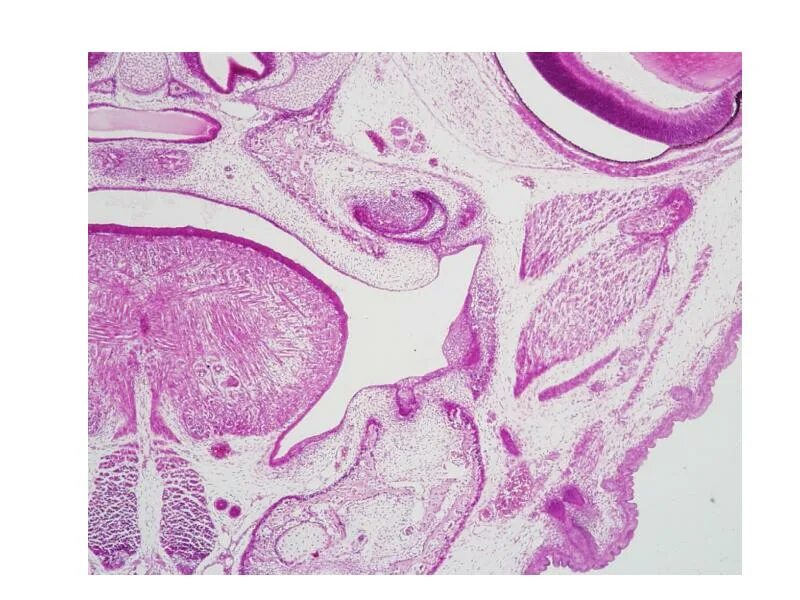

Гистология пищеварительная